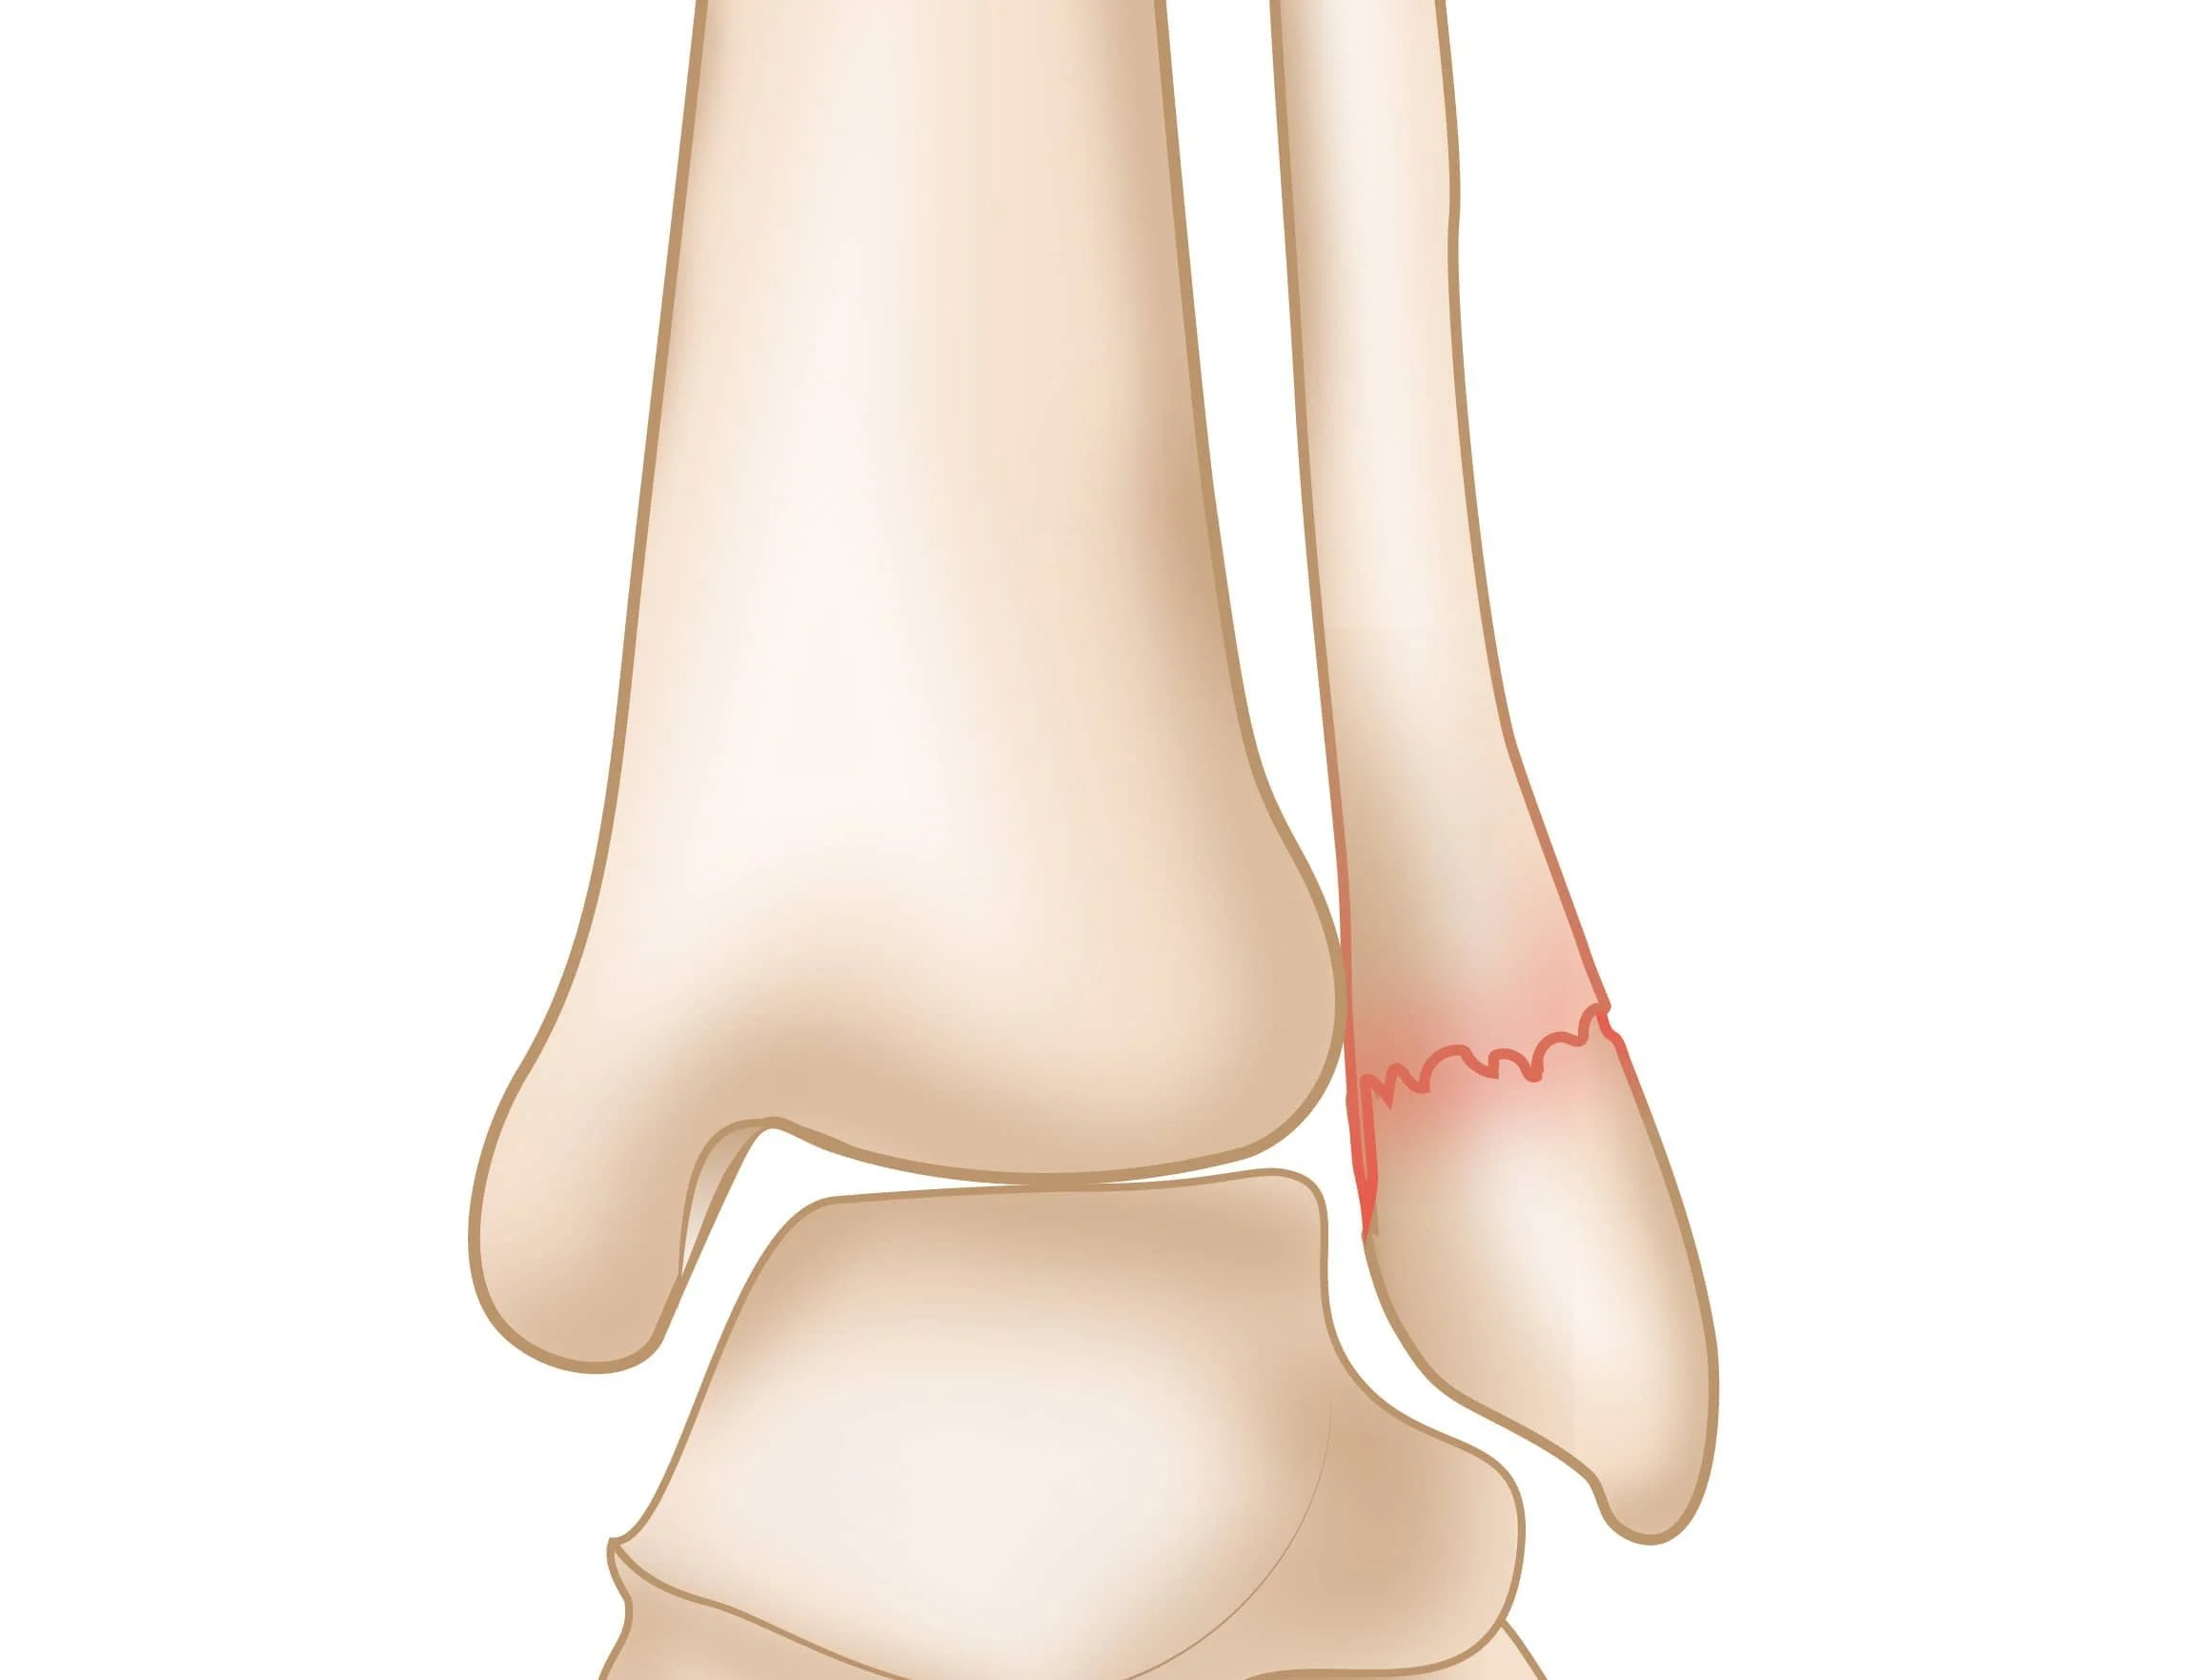

Illustration of a human ankle with a highlighted area showing injury or inflammation on the outer side, near the Achilles tendon.

Ankle Fracture (Open Reduction Internal Fixation)

An ankle fracture can destabilize the joint and make walking painful or unsafe. Surgical fixation (ORIF) repositions and secures the broken bones with hardware to restore proper alignment, prevent arthritis, and allow a stable return to activity.